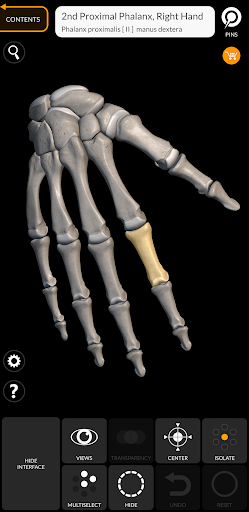

"Skeleton | 3D Atlas of Anatomy" is a next generation anatomy atlas in 3D which gives you availability of interactive highly detailed anatomical models!

Each bone of the human skeleton has been reconstructed in 3D, you can rotate and zoom in on each model and observe it in detail from any angle.

By selecting models or pins you will be shown the terms related to any specific anatomical part, you can select from 12 languages and show the terms in two languages simultaneously.

HIGHLY DETAILED ANATOMICAL 3D MODELS

• Accurate 3D modeling

• Surfaces of the skeleton with high resolution textures up to 4K

• Rotate and Zoom every model in the 3D space

• Division by regions for a clear and immediate visual of each structure

• Interactive Pin allow visualization of the term relative to every anatomical detail